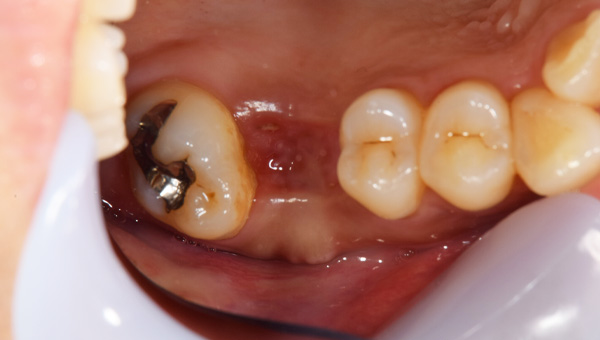

初診時の口腔内

説明:

初診時の口腔内です。かぶせ物があり、一見虫歯とはわからないです。

初診時のパノラマ

初診時のパノラマです。左下の一番奥の歯が虫歯になっているのがわかります。